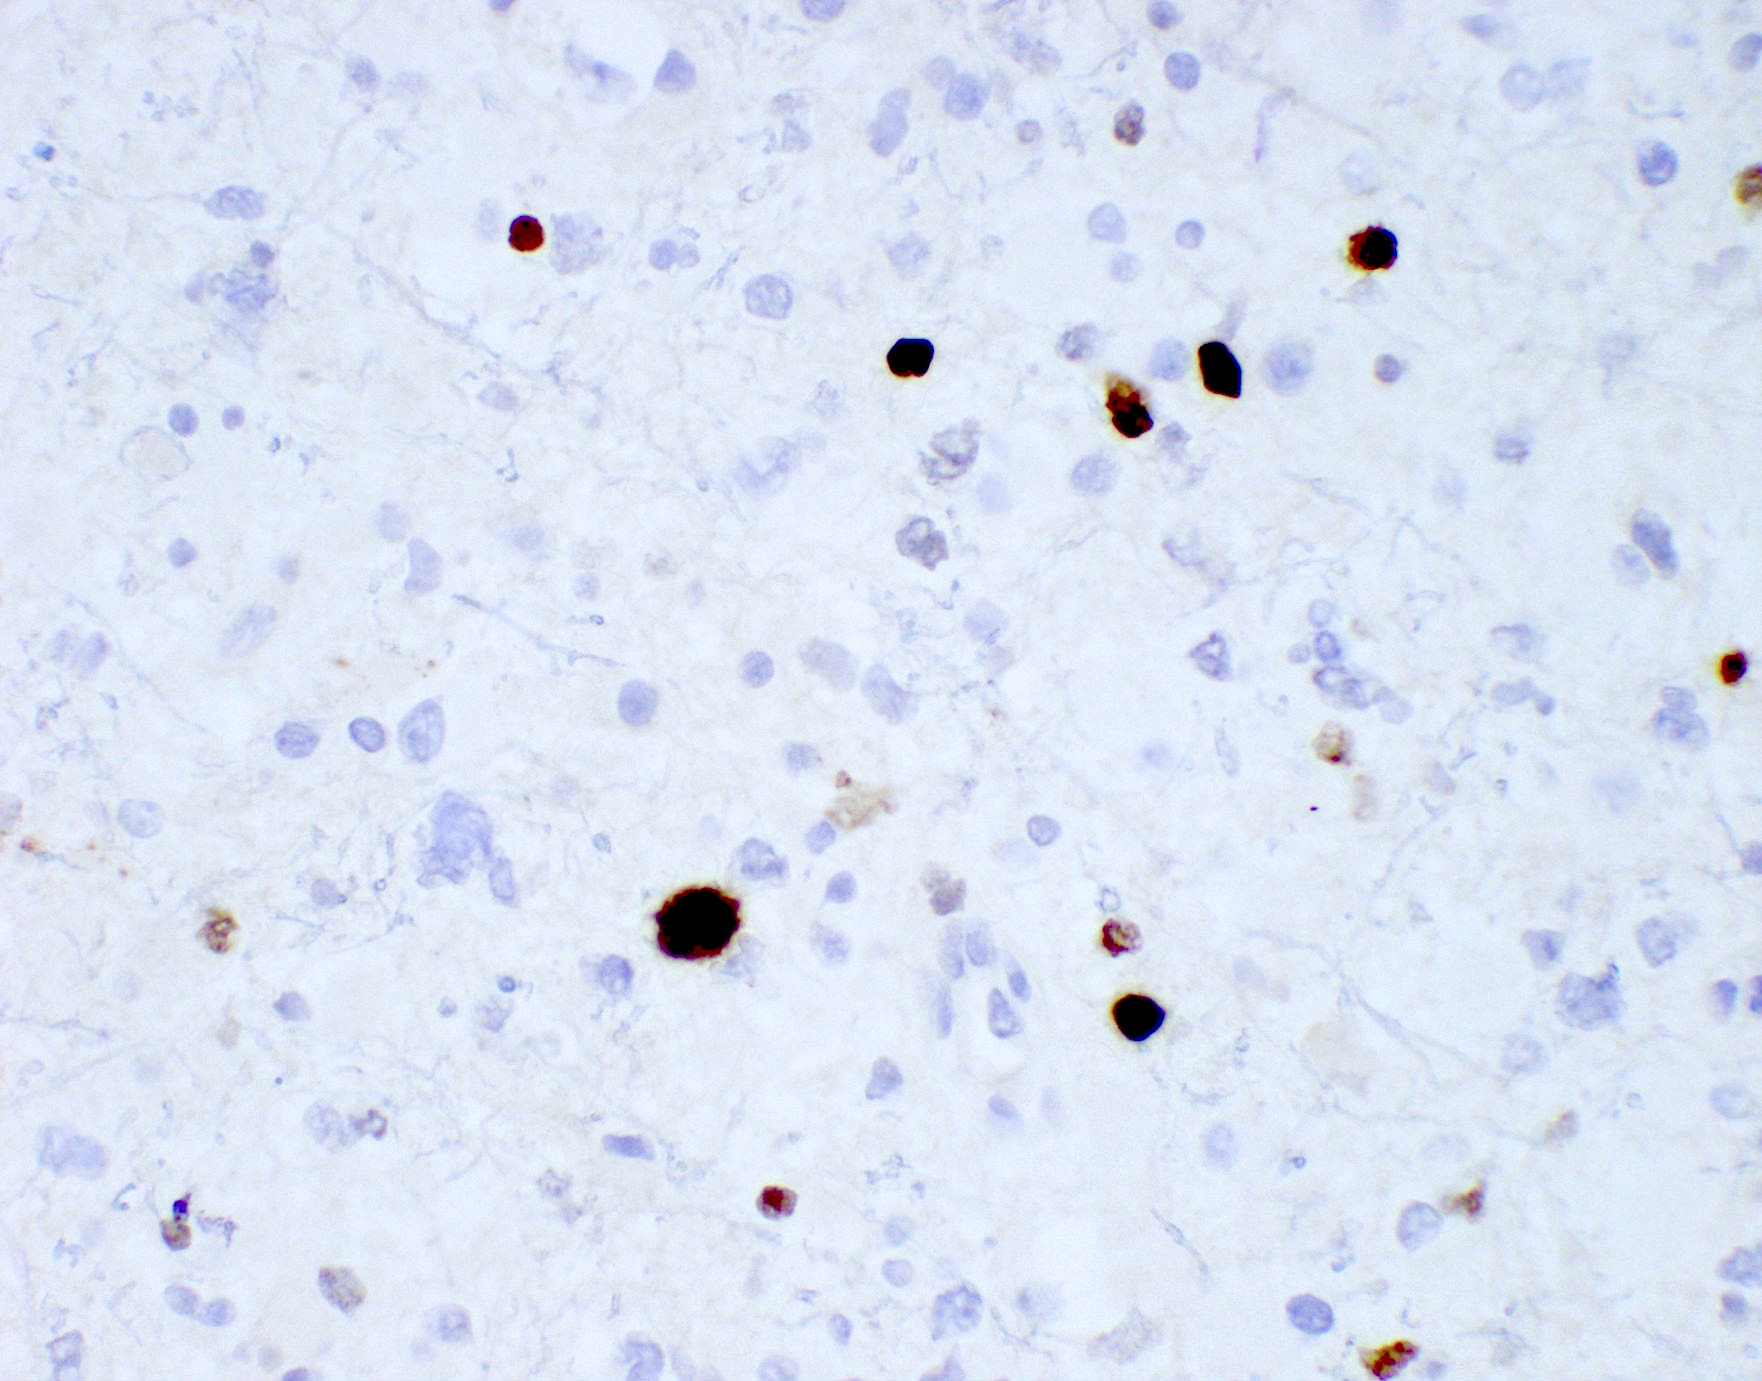

Positive stains

Negative stains

- ATRX

- Loss of nuclear ATRX is typical of diffuse astrocytomas, not oligodendrogliomas or reactive gliosis (Front Oncol 2017;7:236)

- Strong nuclear expression in nonneoplastic vasculature and cells serves as an internal control

- p53 mutation and ATRX promoter mutation nearly always present (typically absent in oligodendroglioma, IDH mutant and 1p19q codeleted) (N Engl J Med 2015;372:2481)

- ATRX: nuclear expression lost (consistent with mutant)